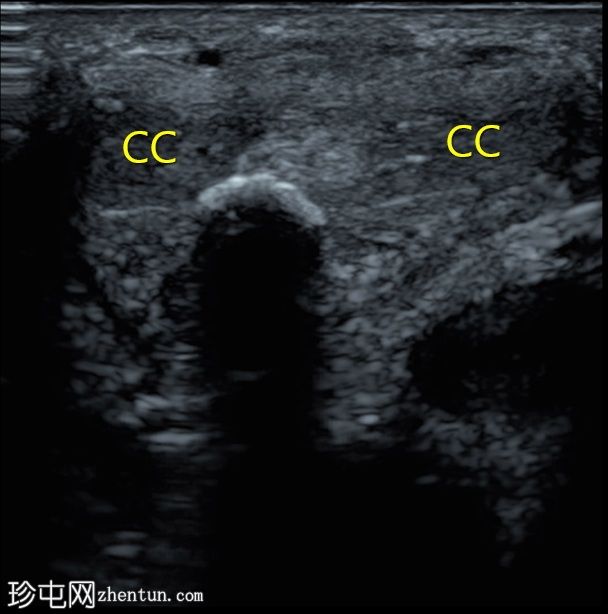

纵切面

阴茎腹侧白膜内可见一纤维钙化斑块,位于阴茎海绵体和尿道海绵体之间。

阴茎海绵体内可见另一条线状纤维钙化斑块(横切面未显示)。

阴茎隔未受累。

白膜内的纤维钙化斑块提示佩罗尼氏病。

该条状回声伴后方声影,形似眉毛。